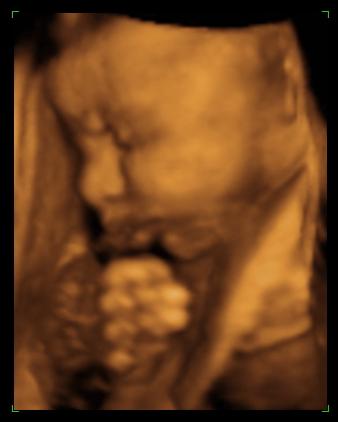

Kép